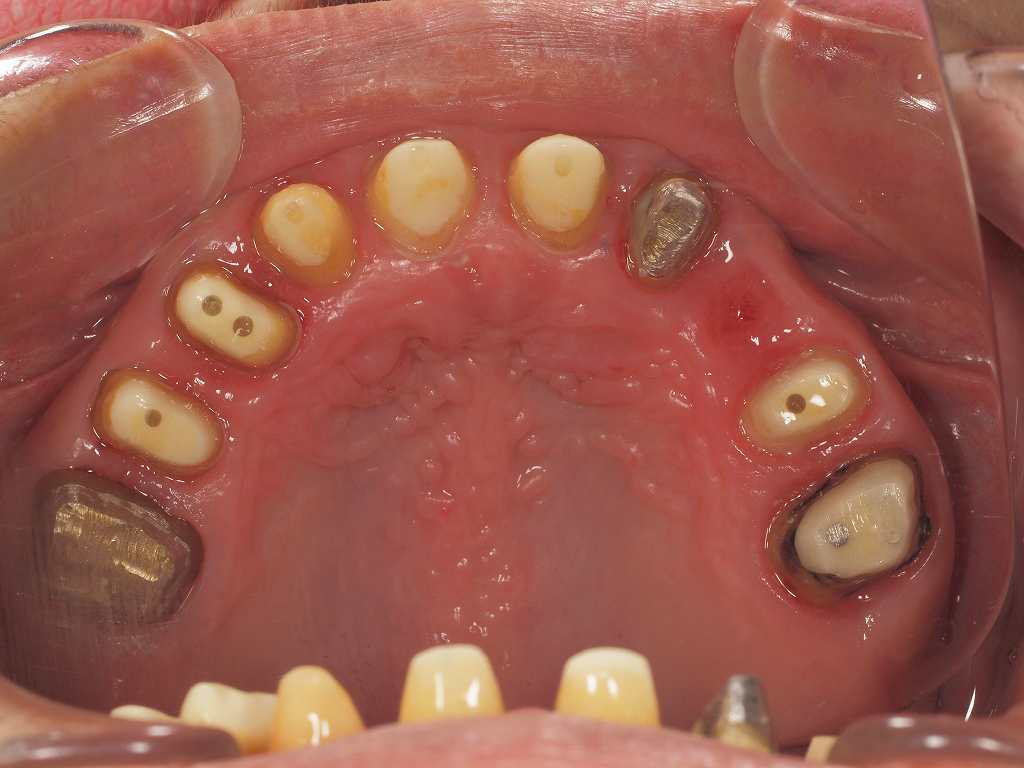

フルマウスのリコンストラクション 咬合再構成 保険治療 50代後半男性 歯が動揺したり、ところどころ欠損すると最終的にはこのようになります

欠損歯もあり、動揺歯もあるとこのようにつなげていかなければ、歯は持ちません

奥歯は銀歯になりますが、、、動揺歯をしっかり固定することで

長持ちしやすい補綴物となりました